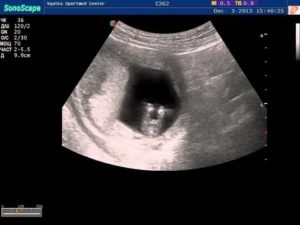

На момент, когда уже можно делать ваше первое узи при наличии беременности, диаметр плодного яйца всего около 5 мм. Для определения точного срока необходимо измерить размер эмбриона от головки до копчика.

Вероятность ошибки в данном случае не больше трех дней.